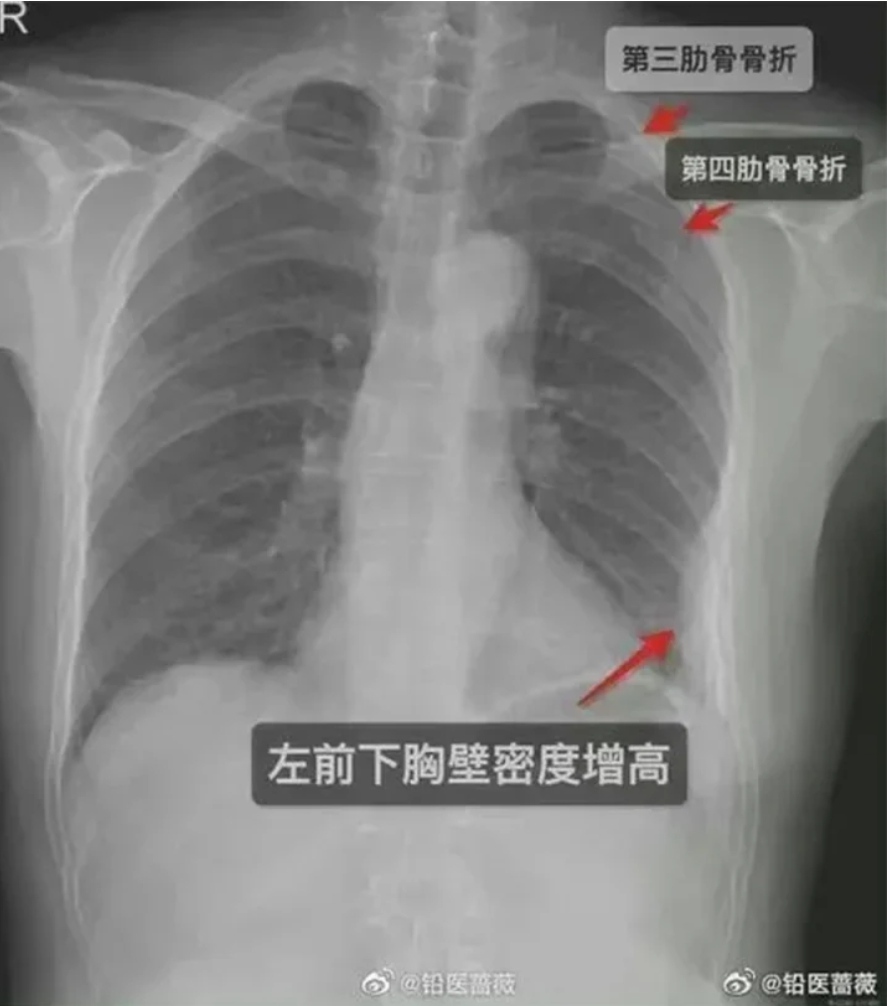

‘अल्ट्रा टाइट’ अँगालो हालेको पाँच दिनपछि ती महिलाको छाती असाध्यै दुख्न थाल्यो । उनी अस्पताल नगई बस्न सकिनन् । एक्स रे गरेर हेर्दा उनको एउटा मात्रै नभई तीनवटा करङ भाँच्चिएको पत्ता लाग्यो । दुईवटा दाहिने पट्टी र एउटा देब्रे पट्टी । छाती दुखेपछि उनी बाध्यतावश घर बस्नुपरेको, घर बस्दा कमाई नभएको र मेडिकल बिल र नर्सिङ सेवाका लागि राम्रै रकम खर्च भएको उनले बताएकी छिन् ।